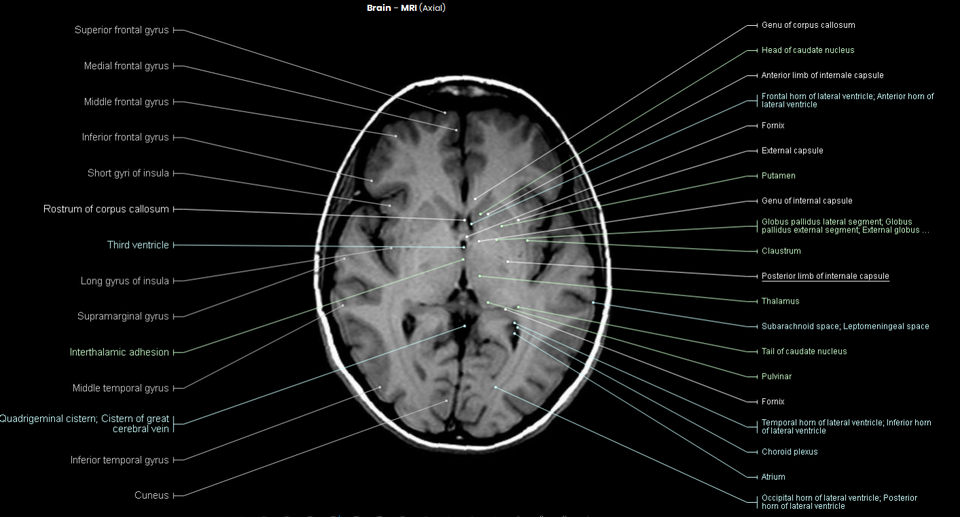

Axial Mri Brain Labeled . Scroll through the images on the left. Citation, doi, disclosures and article data. Anterior cerebral artery from carotid bifurcation to anterior. On the axial mri brain scan, the thalamus is seen as a dark gray ovoid mass, found immediately lateral to the third ventricle and deep to the lateral ventricle. Mri axial cross sectional anatomy of brain. Note, however, that mcrae’s line (basion to the opisthion) needs. This article lists a series of labeled imaging anatomy cases by body region. Radiologists use brain mri to diagnose diseases such as migraine, stroke, microvascular ischemic disease, dementia, multiple sclerosis, epilepsy,. Citation, doi, disclosures and case data.

On the axial mri brain scan, the thalamus is seen as a dark gray ovoid mass, found immediately lateral to the third ventricle and deep to the lateral ventricle. This article lists a series of labeled imaging anatomy cases by body region. Citation, doi, disclosures and article data. Anterior cerebral artery from carotid bifurcation to anterior. Citation, doi, disclosures and case data. Mri axial cross sectional anatomy of brain. Note, however, that mcrae’s line (basion to the opisthion) needs. Radiologists use brain mri to diagnose diseases such as migraine, stroke, microvascular ischemic disease, dementia, multiple sclerosis, epilepsy,. Scroll through the images on the left.